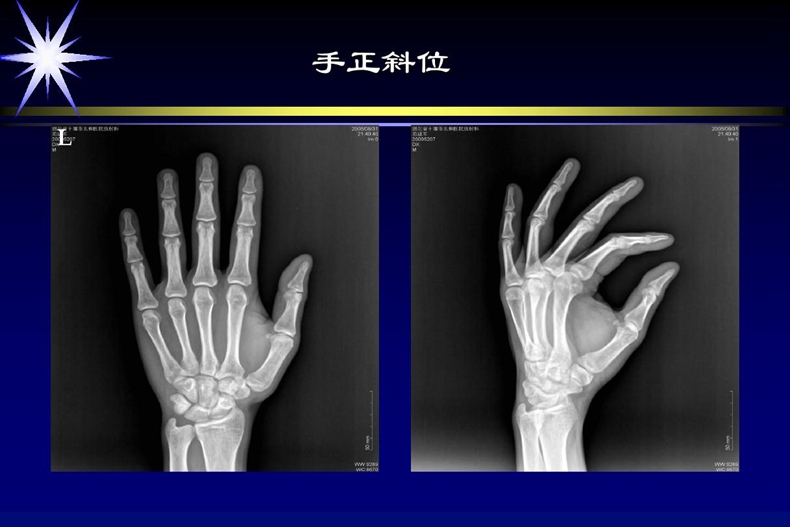

“醫(yī)學(xué)影像學(xué)”專業(yè),學(xué)制應(yīng)為五年,授予學(xué)位是醫(yī)學(xué)學(xué)士。學(xué)生的培養(yǎng)目標(biāo)是“具有基礎(chǔ)醫(yī)學(xué)、臨床醫(yī)學(xué)專業(yè)課程和現(xiàn)代醫(yī)學(xué)影像學(xué)的基本理論知識(shí)及能力,能在醫(yī)療衛(wèi)生單位從事醫(yī)學(xué)影像診斷、介入放射學(xué)和醫(yī)學(xué)成像技術(shù)等方面工作的醫(yī)學(xué)高級(jí)專門人才”。按照這一培養(yǎng)目標(biāo):學(xué)生就業(yè)后,既能從事醫(yī)學(xué)影像診斷醫(yī)師工作,也能從事醫(yī)學(xué)影像技師工作。四年制醫(yī)學(xué)影像學(xué)專業(yè)是國家為適應(yīng)醫(yī)療衛(wèi)生事業(yè)改革和發(fā)展形勢(shì)的需要,滿足醫(yī)療衛(wèi)生崗位對(duì)人才的需求而設(shè)置的本科專業(yè),按照教育部文件規(guī)定,四年制醫(yī)學(xué)影像專業(yè)授予學(xué)位是理學(xué)學(xué)士。